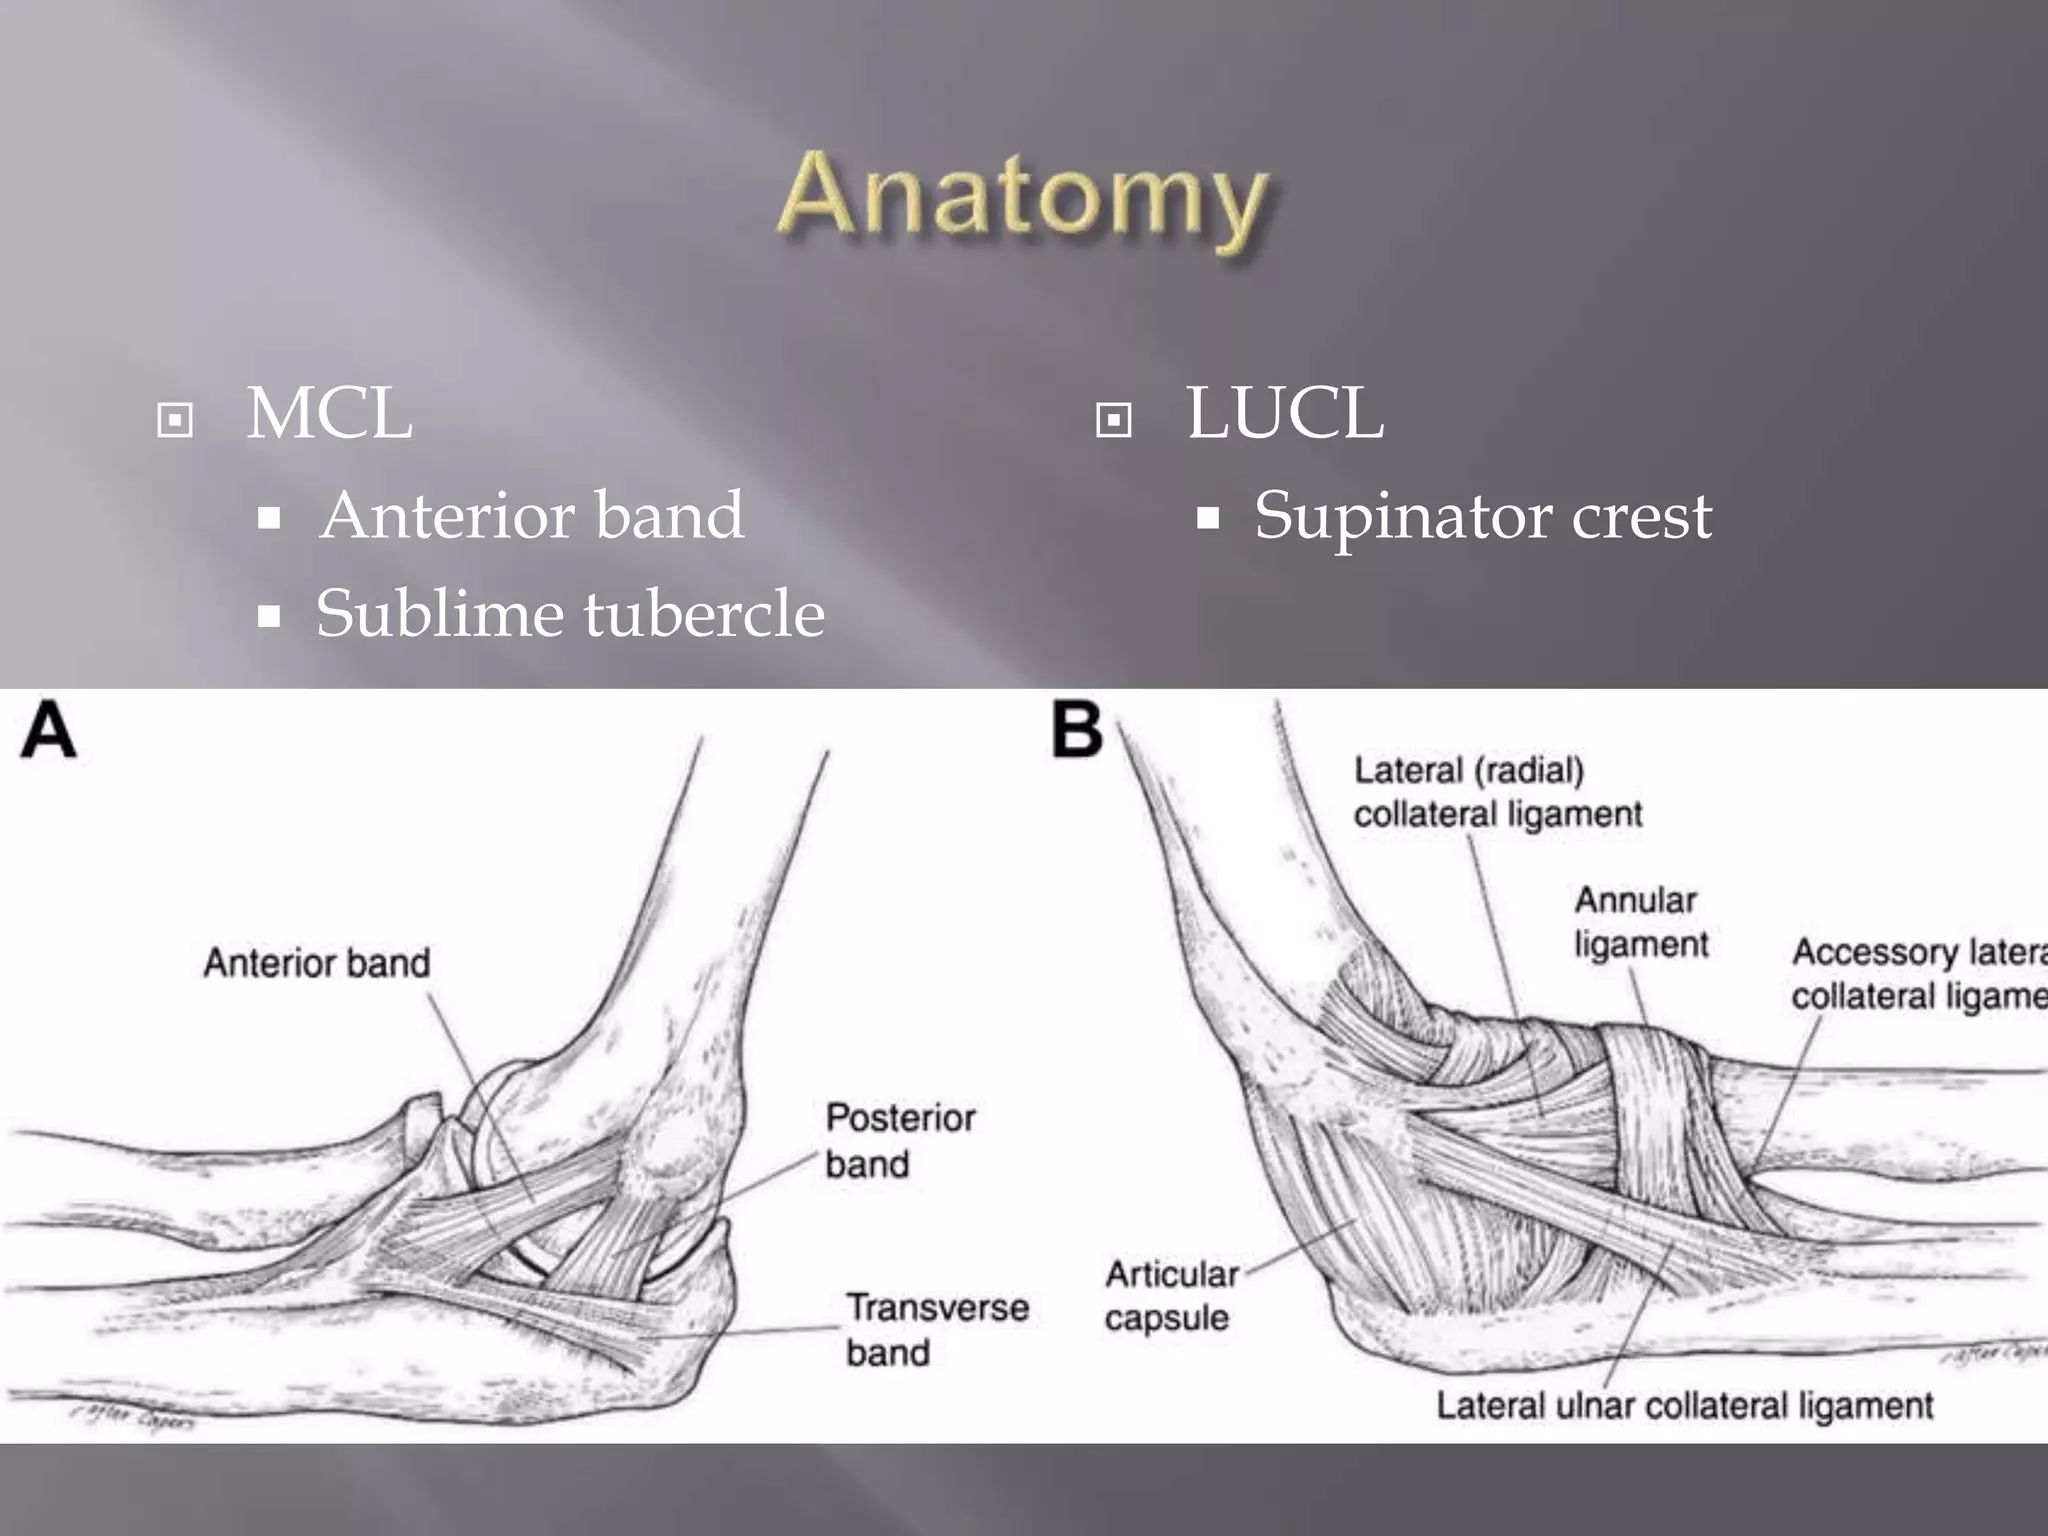

This document discusses the terrible triad injury of the elbow, which involves fractures of the radial head, coronoid process, and posterolateral dislocation. It notes the poor outcomes associated with this injury like stiffness, instability, and hardware failure. The document outlines the relevant anatomy of the medial collateral ligament and lateral uncular collateral ligament. It describes the mechanism of injury, known as the fall on an outstretched hand, and how the ligaments and capsule fail in this injury. Diagnostic imaging and classification of radial head and coronoid fractures are covered. Treatment options including observation, resection, open reduction internal fixation, and replacement are presented. Surgical approaches and techniques are also outlined.